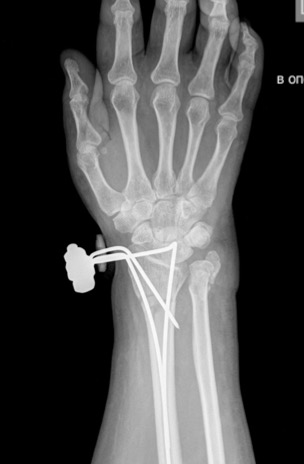

Здравствуйте, Александр Николаевич! Такой вариант я, находясь у Вас на учебе, видел и рассматривал. Но у меня перелом лучевой кости внутрисуставной и локтевая сломана. В итоге то, что придумалось мне показалось приемлемее.

Р-грамма после репозиции.

Здравствуйте,по снимкам неплохо. А какая причина отказа от открытой репозиции, остеосинтеза пластинами? Финансовая? Сохраняется смещение отломка Локтевой кости с диастазом между отломками. Не критично? Может наступить замедленная консолидация..

Можно сказать, что финансовая. Кое что по бюджетной закупке у нас есть, но в полном объеме, для такого случая фиксаторов не хватает. По поводу смещения локтевой, согласен. Я с нее начинал - стояло хорошо, а когда работал с лучевой появилось такое смещение. С учетом нормального соотношения в суставе и допустимой оси локтевой кости, я решил остановиться. Все выполнялось закрыто, в виду чего я надеюсь на своевременное сращение.